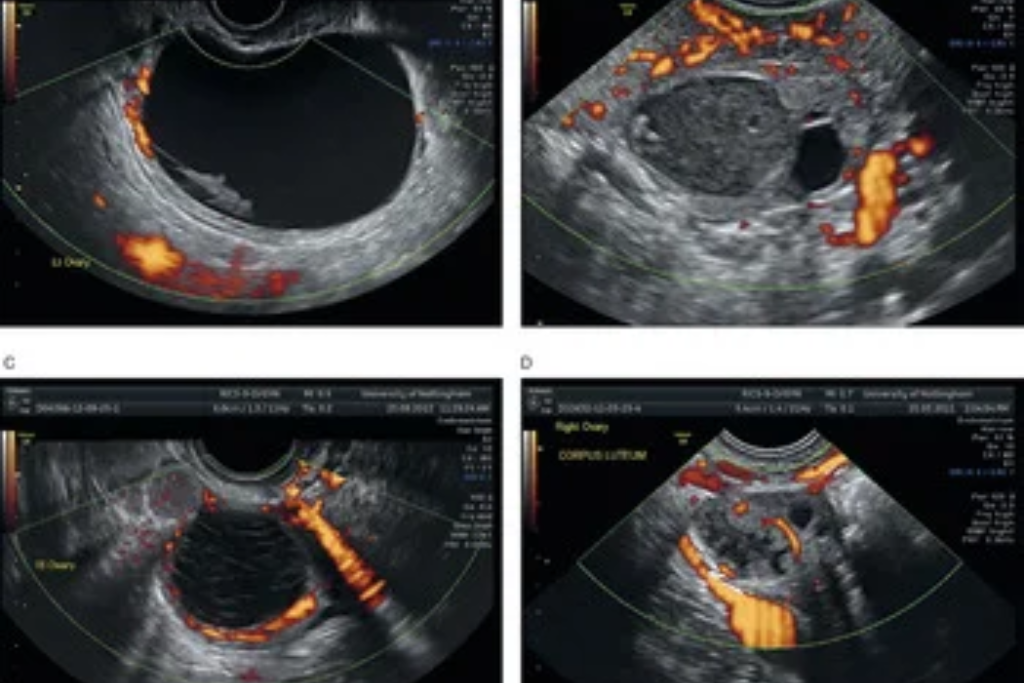

Doppler Ultrasonography

A type of ultrasound used to measure blood flow and its speed in vessels.